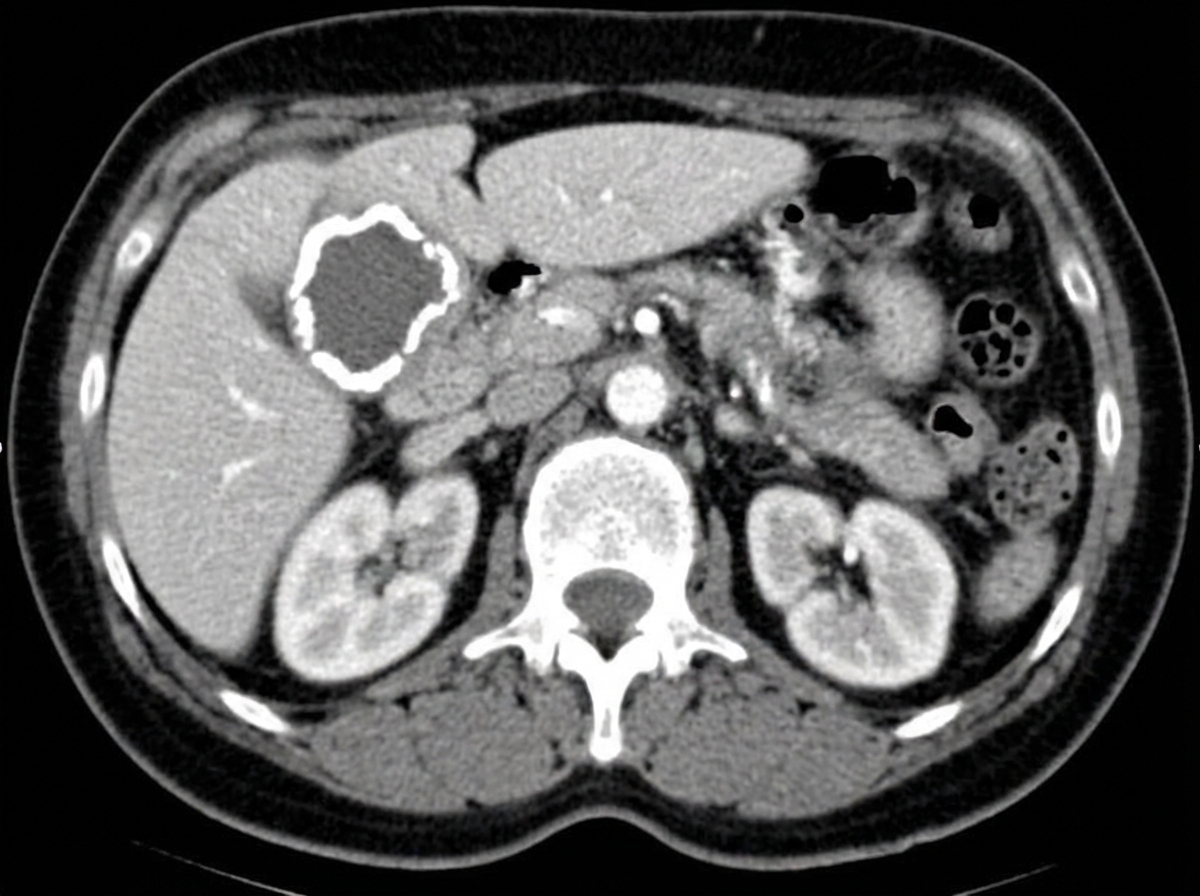

A 60-year-old woman comes to the physician because of intermittent abdominal pain for the past month. The patient reports that the pain is located in the right upper abdomen and that it does not change with food intake. She has had no nausea, vomiting, or change in weight. She has a history of hypertension and hyperlipidemia. She does not smoke. She drinks 1–2 glasses of wine per day. Current medications include captopril and atorvastatin. Physical examination shows a small, firm mass in the right upper quadrant. Laboratory studies are within the reference range. A CT scan of the abdomen is shown. This patient's condition puts her at increased risk of developing which of the following?